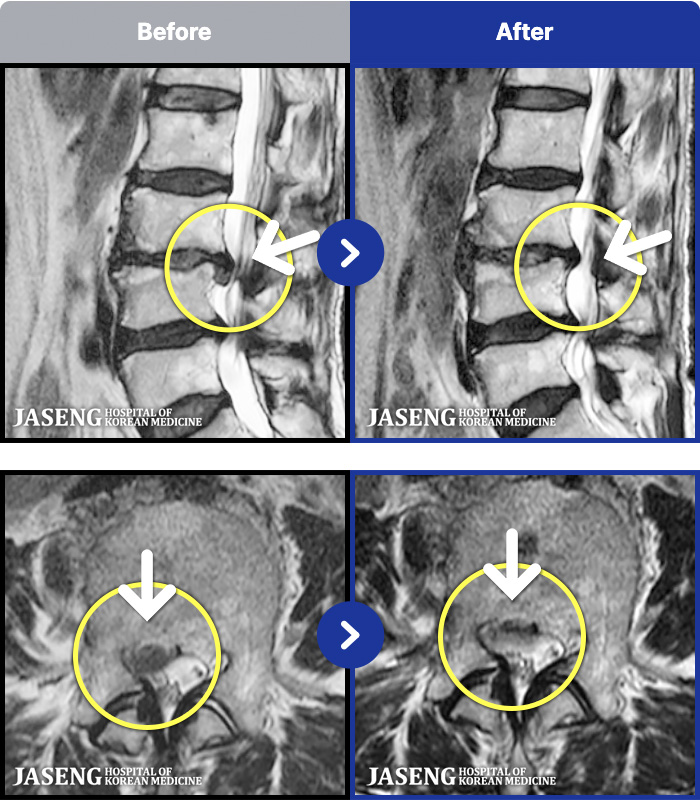

1,287 MRI ũ ʸ Ȯϼ.

[ϻ] 24.07.25~25.08.01